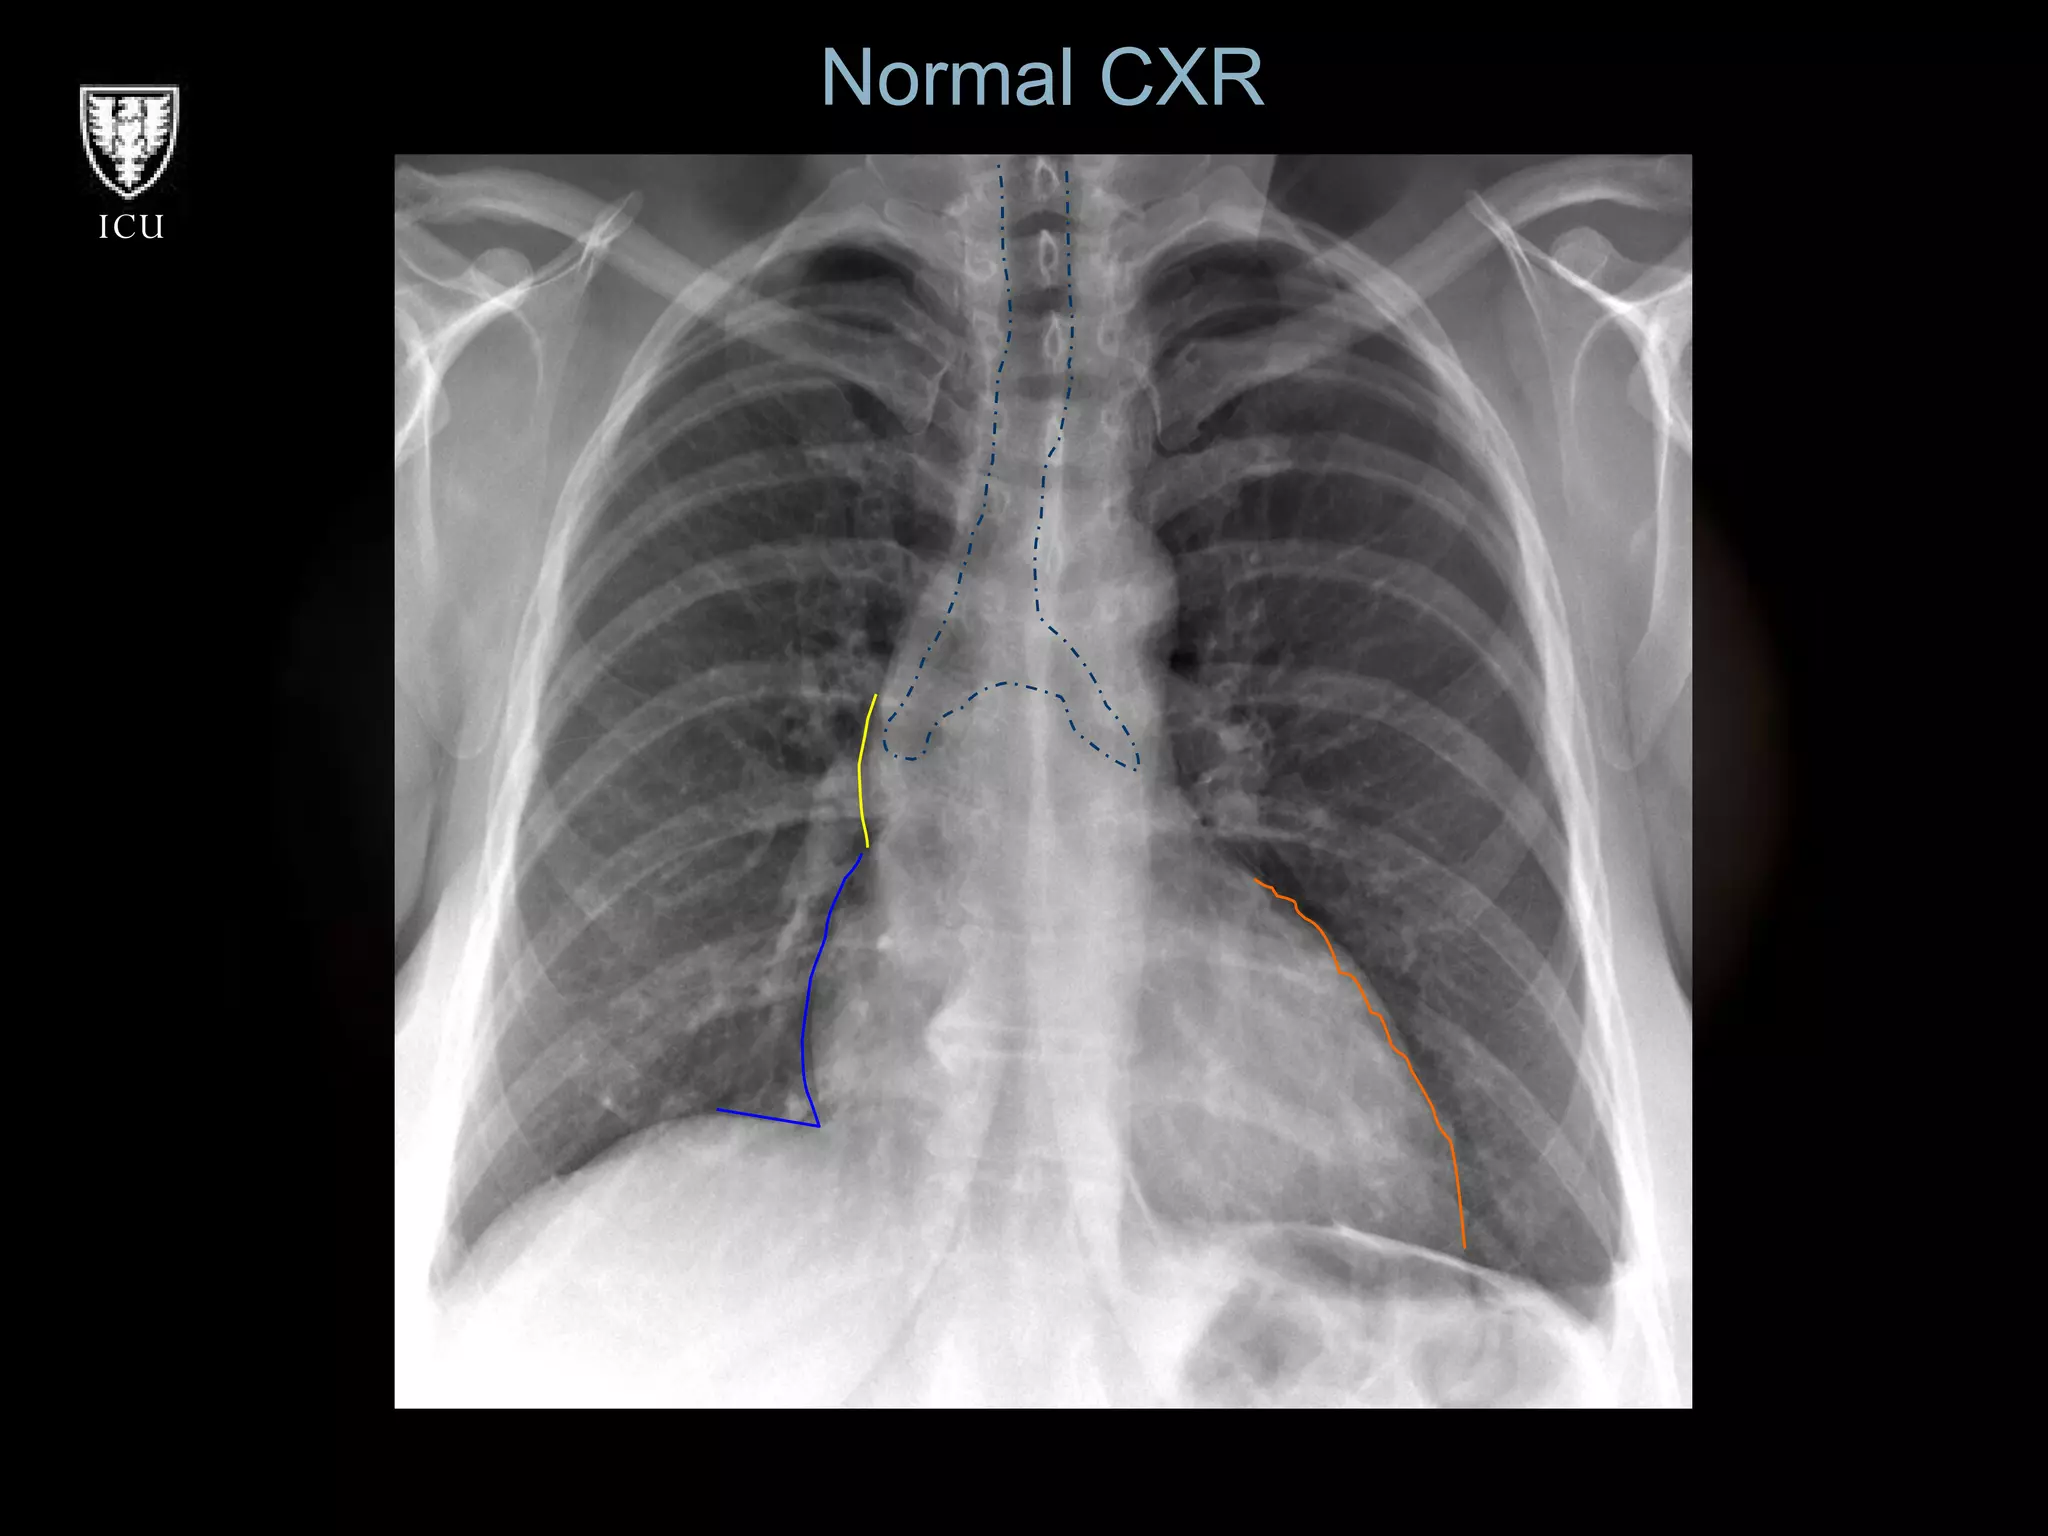

Normal CXR

Prevention of Mechanical Complications Ultrasound Guidance  -Useful for internal jugular -Potentially prevents wrong vessel, hemo/pneumothorax Pressure waveform monitor -Arterial cannulation/puncture CXR -Cardiac tamponade -Wire/catheter embolus

Prevention of MechanicalComplications Ultrasound Guidance -Useful for internal jugular -Potentially prevents wrong vessel, hemo/pneumothorax Pressure waveform monitor -Arterial cannulation/puncture CXR -Cardiac tamponade -Wire/catheter embolus